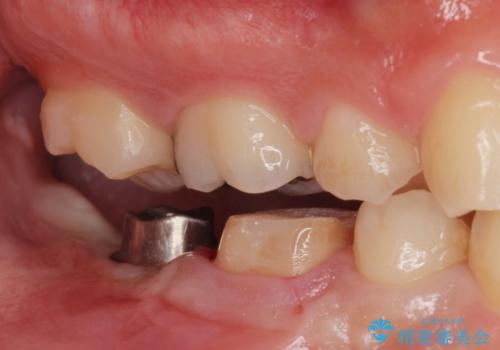

白くて綺麗な被せ物が入りました。

インプラントを入れた後は定期的なメンテナンスが必要になります。